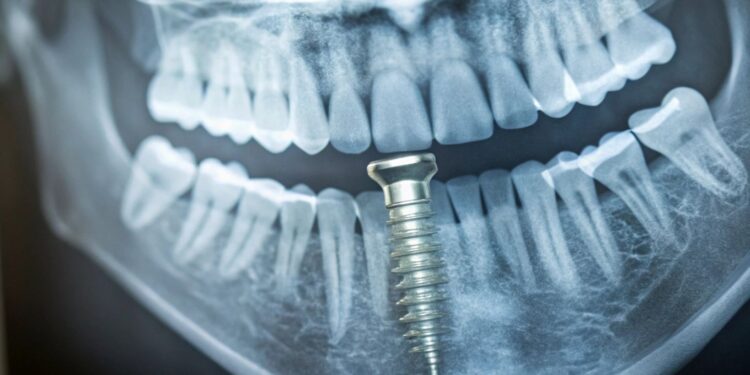

Pterygoid implants are long dental implants placed in the pterygoid region of your upper jaw. This area is near the back of your mouth, where the maxillary tuberosity meets the pterygoid process of the sphenoid bone.

This bone area is dense and strong, making it a good place for implants when your upper jawbone has lost volume. The implants anchor into the pterygoid plates, which are part of the sphenoid bone, allowing better stability without needing bone grafts or sinus lifts.

The placement of pterygoid implants starts with an assessment of your jaw anatomy using scans and exams. During surgery, your dentist will angle the implant to engage the strong pterygoid bone behind the jaw.